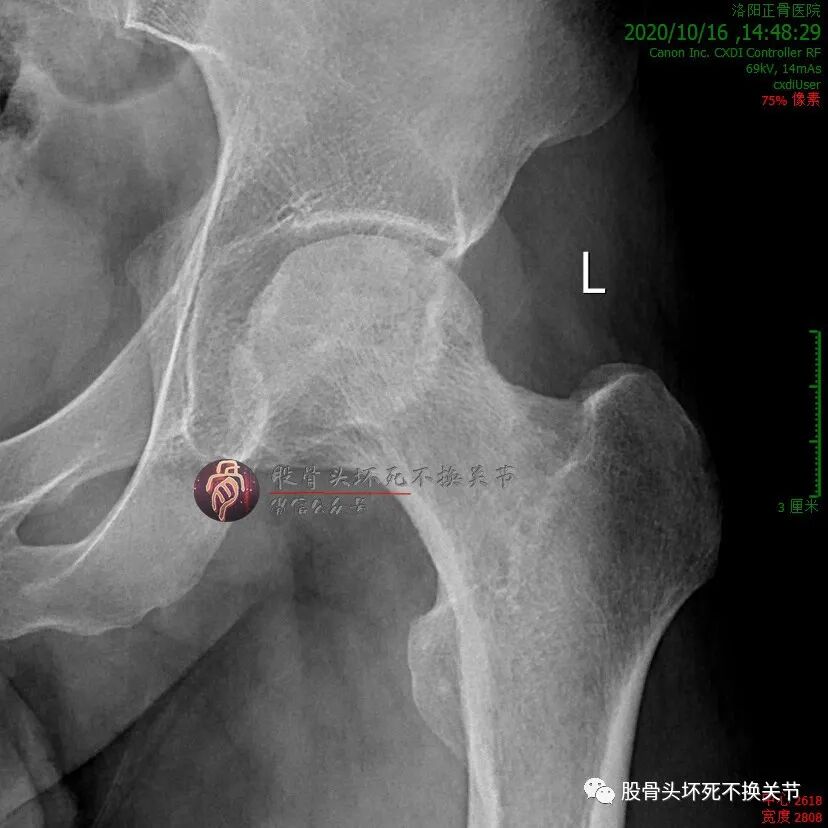

男性,34岁,2019年11月确诊左侧股骨头坏死,2020年1月前来住院行冲击波综合保髋治疗,详情如下:

股骨头内大面积的密度不均减低区就是坏死区。